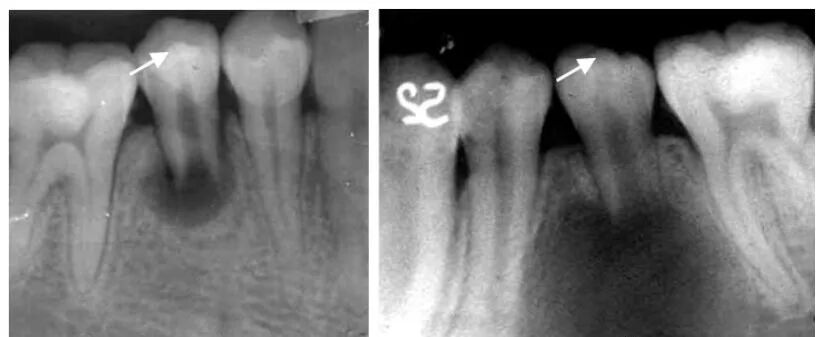

牙槽骨水平型吸收

曲面断层片怎么看正畸【曲面断层片(全景片)】如何解读和查看:牙周?牙体?牙髓?关节?_https://www.jmylbn.com_新闻资讯_第13张

多数牙或全口牙槽骨从嵴顶呈水平方向向根尖高度减低,吸收程度较均匀,早期表现牙槽嵴顶骨硬板模糊,继而前牙区牙槽嵴顶由尖变平,后牙区牙槽嵴顶由梯形变凹陷,边缘模糊粗糙呈虫蚀样;随疾病进一步发展,牙槽嵴逐渐向根尖方向吸收。

牙槽骨垂直型吸收

曲面断层片怎么看正畸【曲面断层片(全景片)】如何解读和查看:牙周?牙体?牙髓?关节?_https://www.jmylbn.com_新闻资讯_第14张

表现为局部牙槽骨或牙槽间隔的一侧,沿牙体长轴方向向根端吸收,病变早期造成牙槽骨壁吸收,骨硬板消失,牙周间隙增宽;随病变加重,牙槽骨垂直吸收明显,呈楔形,若同一牙齿近远中均有垂直吸收,牙槽骨可见弧形吸收(吸收区域包绕两个及以上牙面)。